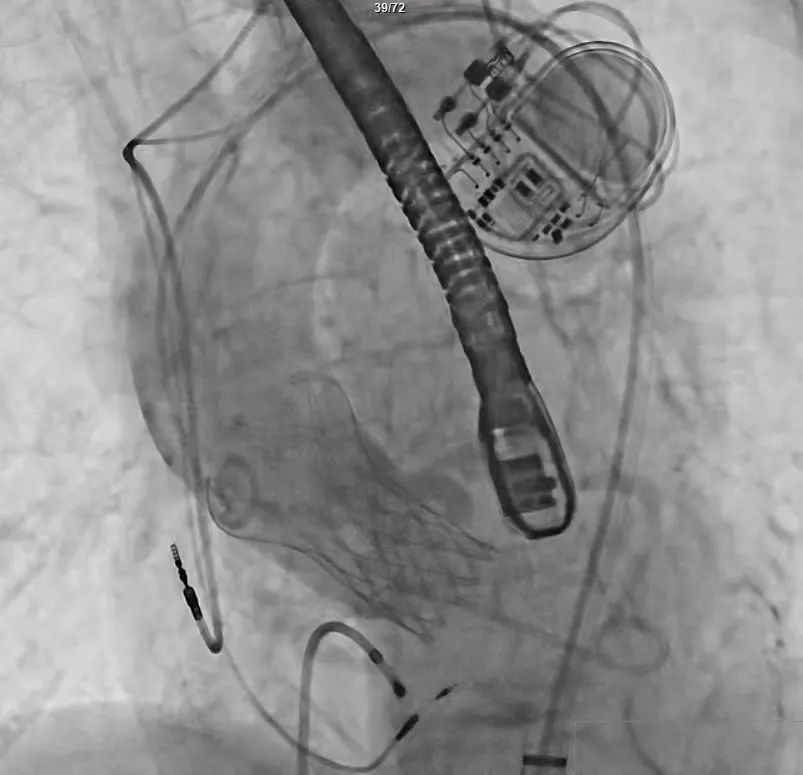

手术过程严谨有序:经术前精准评估与周密准备,团队成功送入预先装载的自膨式支架瓣膜输送系统,顺利完成过弓、跨瓣操作;经造影定位后,在180bpm快速起搏下精准释放瓣膜。瓣膜释放后,术中实时超声显示根部瓣架形态良好、启闭正常,瓣叶中心及瓣周未见反流;造影显示瓣膜位置满意、形态良好,冠脉显影清晰,入路血管无损伤,历经90分钟后,手术圆满成功。

术中影像